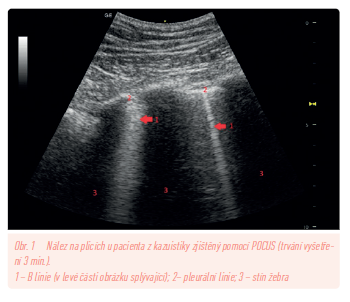

Při příchodu do ordinace byla pacientka eupnoická, s tělesnou teplotou 37,5 °C. Výsledek fyzikálního vyšetření byl jinak normální včetně poslechového a poklepového nálezu na plicích. Akce srdeční klidná, tepová frekvence 75/min, bez šelestu, saturace arteriální krve kyslíkem 97 %, C‑reaktivní protein (CRP) POCT (Point‑of‑Care Testing) 65 mg/l, D‑dimery POCT 0,1 µg/ml, fyziologická EKG křivka. Součástí vyšetření bylo i provedení Point‑of‑Care ultrasonografického vyšetření pleury a plic protokolem BLUE (Basic Lung Ultrasound Examination). Toto vyšetření prokázalo difuzní oboustranný B profil ve všech vyšetřovacích bodech se splývajícími B liniemi, se zachovalým pleurálním slidingem, s drobnými nepravidelnostmi pleury, bez známek plicní konsolidace (obr. 1). Na základě provedených vyšetření byla stanovena pracovní diagnóza oboustranné covidové pneumonie a pacientka byla odeslána k hospitalizaci do lokální nemocnice (v dané době bylo v České republice nedostupné podání specifických monoklonálních protilátek a ambulantní léčba pneumonie nebyla doporučována). Všechna uvedená vyšetření byla provedena v ordinaci všeobecného praktického lékaře během 20 minut.